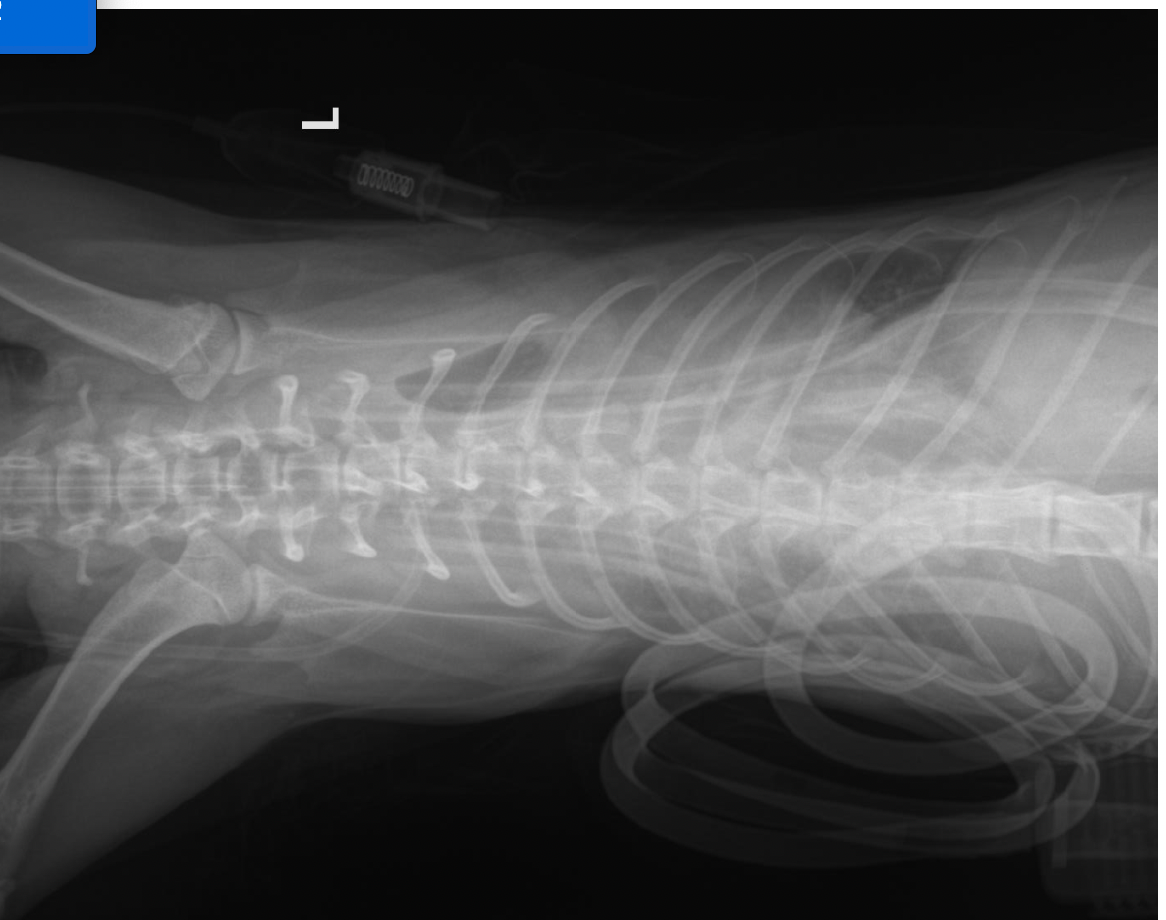

Ca is a 7-month-old feral kitten born in my neighborhood. I had already spayed her mom and planned to spay Ca once she reached the minimum age requirement for the local hospitals. However, she disappeared, and when I eventually found her, she was in very poor condition. After taking her to the vet, she was diagnosed with a broken leg (likely from a car accident), severe inflammation, and empyema.

During the first drainage, they managed to extract 115 ml of fluid from her abdomen, and her condition stabilized for only one day. The second drainage, however, couldn’t remove anything due to the thickness of the pus. We had to transfer her to a better hospital for thoracostomy surgery, where they discovered that one side of her lung had already collapsed.

I have already covered her expenses so far on my own. However, she’s still in the ICU, and the medical bills are increasing quickly due to the hospitalization costs, the frequent X-ray scans, and the monitoring of her blood indicators. I also encountered some financial difficulties with regards to family issues recently, I guess it's just a bad timing for both me and her.

J’ai décidé de la transférer vers un autre hôpital qui pouvait réaliser une chirurgie qui pouvait améliorer son état. Là-bas, j’ai appris qu’un de ses poumons s’était affaissé. Elle a subi une chirurgie complexe pour poser des tubes de drainage et a été admise en soins intensifs.